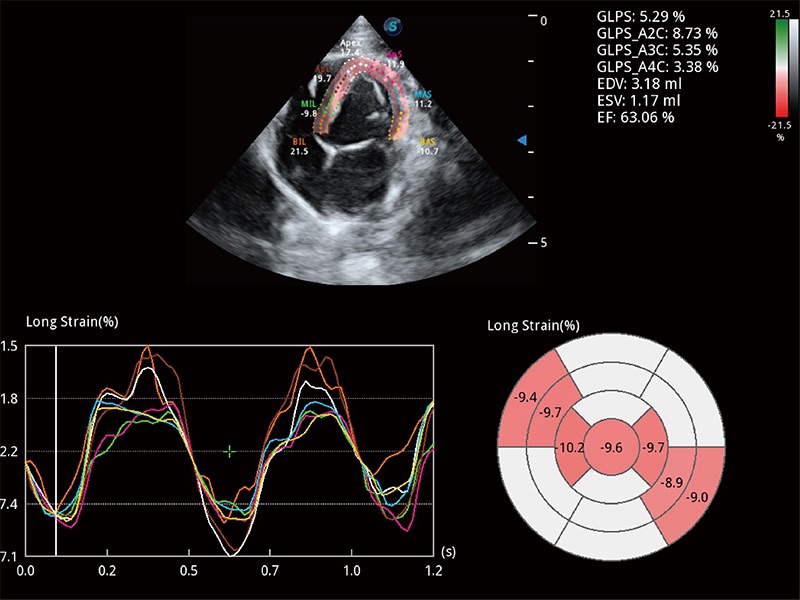

实时用颜色表示心肌组织运动,观察和定量组织的运动情況,对快速检测与评估心肌的灌注和活性、电传导及心肌收缩和舒张功能等均能提供重要的诊断信息。

通过心肌识别技术与二维斑点追踪技术相结合,对心脏的超声图像进行量化分析。计算心肌17个节段的应变、应变率、速度、位移等,并通过牛眼图的形式进行呈现。

能够基于左心室壁追踪和辛普森法,自动计算射血分数,支持多个可移动点描迹,与手动测量相比,极大节省了动物医生的时间和精力。